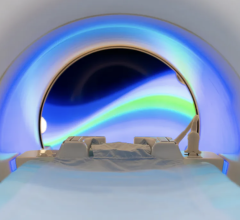

NIH researchers found that dark rimmed spots representing ongoing, “smoldering” inflammation, may be a hallmark of more disabling forms of multiple sclerosis. Image courtesy of Reich lab, NIH/NINDS.

August 22, 2019 — Aided by a high-powered brain scanner and a 3-D printer, National Institutes of Health (NIH) researchers peered inside the brains of hundreds of multiple sclerosis patients. The researchers found that dark rimmed spots representing ongoing, “smoldering” inflammation, called chronic active lesions, may be a hallmark of more aggressive and disabling forms of the disease.

Doctors often use magnetic resonance imaging (MRI) to diagnose patients as the immune system’s attack produces lesions that appear as spots on scans of patients’ brains. While some of the lesions heal, completely or partially, other lesions remain and rimmed ones appear to actively expand, or “smolder”, for many years. Nevertheless, until recently, researchers did not fully understand the role chronic active lesions play in the disease, in part, because it was difficult to find the ones that remain chronically inflamed.

Starting in 2013, Reich’s team showed that by using a high-powered, 7-tesla MRI scanner, they could accurately identify damaging, chronic active lesions by their darkened outer rims, in agreement with previous studies.

“Figuring out how to spot chronic active lesions was a big step and we could not have done it without the high-powered MRI scanner provided by the NIH. It allowed us to then explore how MS lesions evolved and whether they played a role in progressive MS,” said Martina Absinta, M.D., Ph.D., the post-doctoral fellow in Reich’s lab who performed these studies.

Finally, the team used a 3-D printer to compare the spots they had seen on scans to the lesions they observed in brain tissue samples autopsied from a patient who had passed away during the trial. They found that all expanding rimmed spots seen on the scans had the telltale features of chronic active lesions when examined under a microscope.